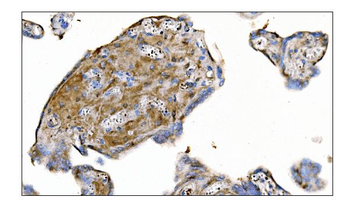

IHC staining of FFPE human colon carcinoma with MerTK antibody (clone TPKR-1). HIER: boil tissue sections in pH9 10mM Tris with 1mM EDTA for 10-20 min and allow to cool before testing.